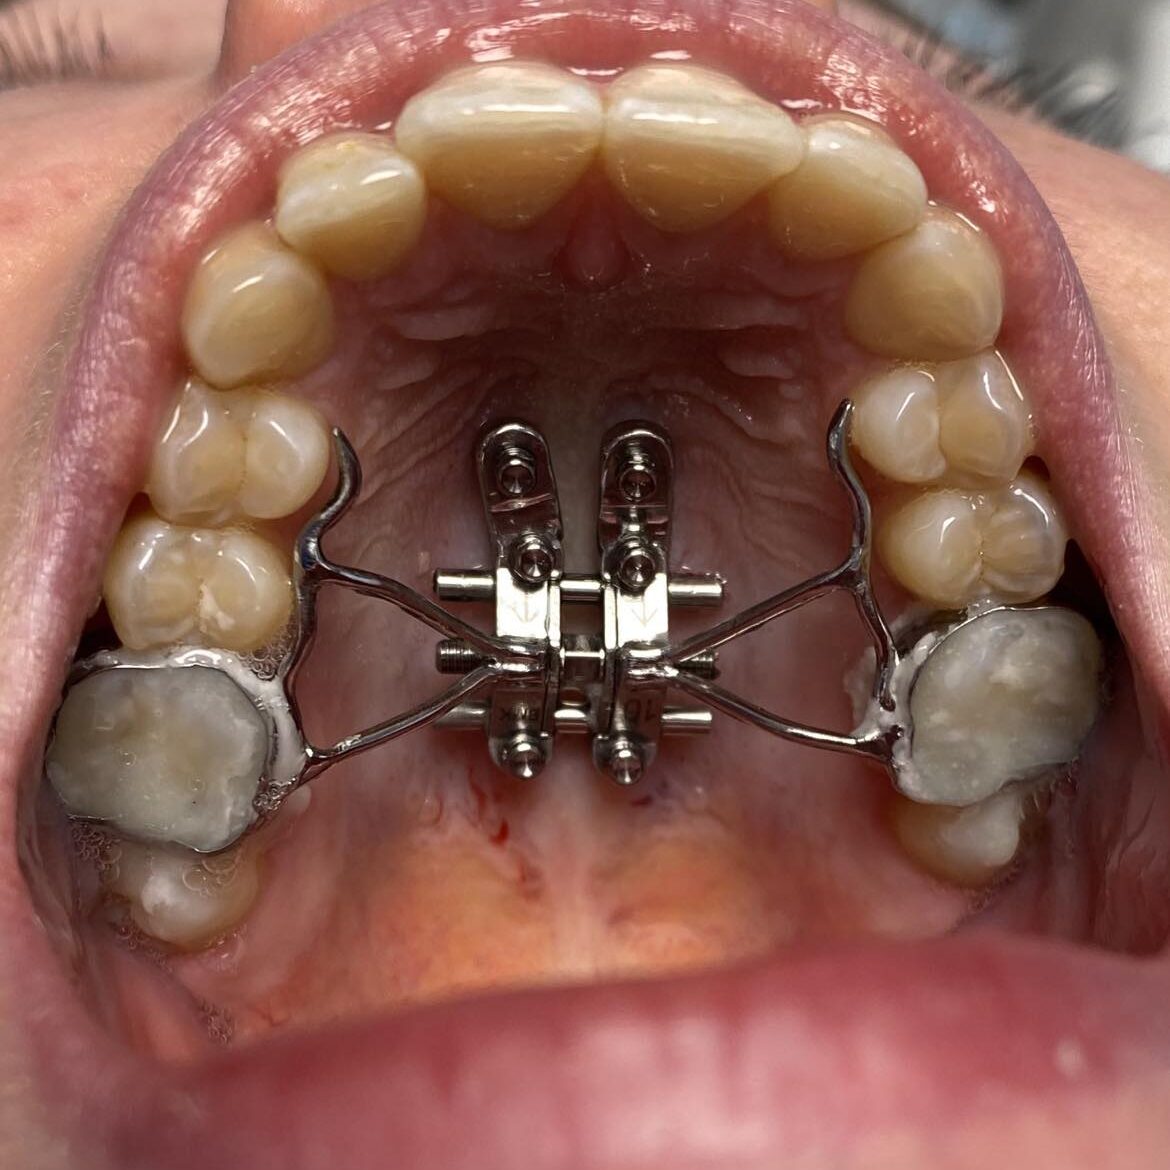

Le MARPE (miniscrew-assited rapid palatal expansion) permet une expansion palatine osseuse sous anesthésie locale au cabinet !

Alors le MARPE est votre ami! En 1 à 3 mois vous avez un nouveau palais élargi et en pleine santé pour :